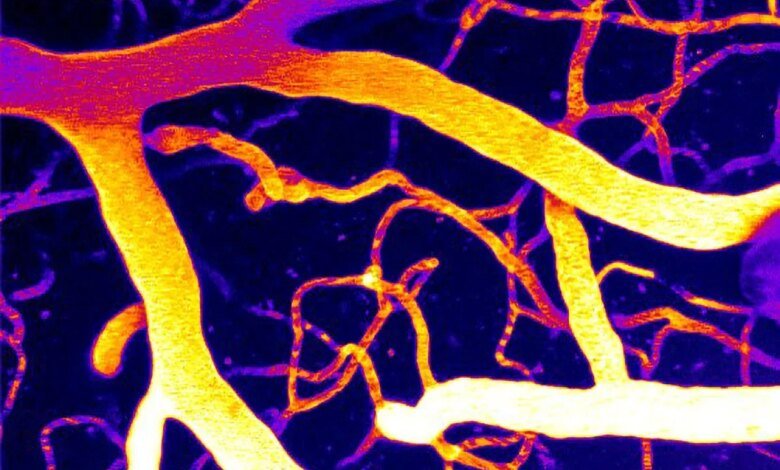

بدأ يظهر نهج جديد محتمل لعلاج انخفاض تدفق الدم في الدماغ وأشكال الخرف ذات الصلة. العلماء في جامعة فيرمونت كشف روبرت لارنر، دكتوراه في الطب بكلية الطب، عن تفاصيل جديدة حول كيفية تنظيم تدفق الدم في الدماغ، مشيرًا إلى طريقة محتملة لإصلاح المشكلات في نظام الأوعية الدموية في الدماغ.

يدرس مختبر حراز كيفية التحكم في تدفق الدم في الدماغ، مع التركيز على إشارات الأوعية الدموية والبروتين المستشعر للضغط المسمى Piezo1 الموجود في خلايا الأوعية الدموية.

تظهر النتائج الجديدة أن Piezo1 يلعب دورًا مهمًا في تنظيم تدفق الدم الدماغي وأن أمراض مثل مرض الزهايمر ترتبط بنشاط Piezo1 المرتفع بشكل غير طبيعي في الأوعية الدموية في الدماغ.

قام فريق حراز بالتحقيق في فسفوليبيد في أغشية خلايا الدماغ يسمى PIP2. يعد هذا الفسفوليبيد ضروريًا لإشارات الخلايا وتنظيم القنوات الأيونية، وهي عملية معقدة حيث تتحكم الخلايا في فتح وإغلاق مسام البروتين. وجد الباحثون أن PIP2 هو مثبط طبيعي لـ Piezo1؛ عندما تنخفض مستويات PIP2، يصبح Piezo1 مفرط النشاط، مما يعطل تدفق الدم في الدماغ.

لقد اختبروا إضافة PIP2 مرة أخرى إلى النظام، مما أدى إلى تثبيط Piezo1 واستعادة تدفق الدم الطبيعي. وتشير الدراسة إلى أن تعزيز PIP2 يمكن أن يصبح استراتيجية علاجية جديدة لاستعادة تدفق الدم الطبيعي وتعزيز وظائف المخ.